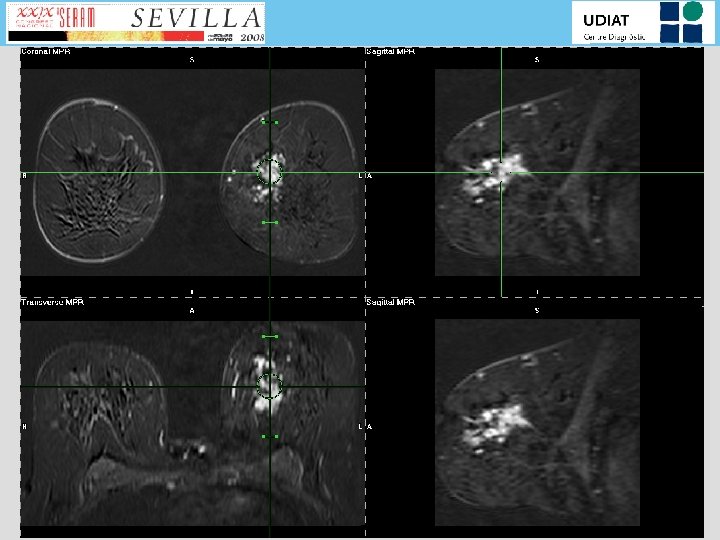

Estudio RM que muestra extensa lesión con captación patológica de contraste de 65 (A-P)

Estudio RM que muestra extensa lesión con captación patológica de contraste de 65 (A-P) x 44 (sup-inf)x 30 (ext-int) mm, localizada en unión de cuadrantes internos de mama izquierda.